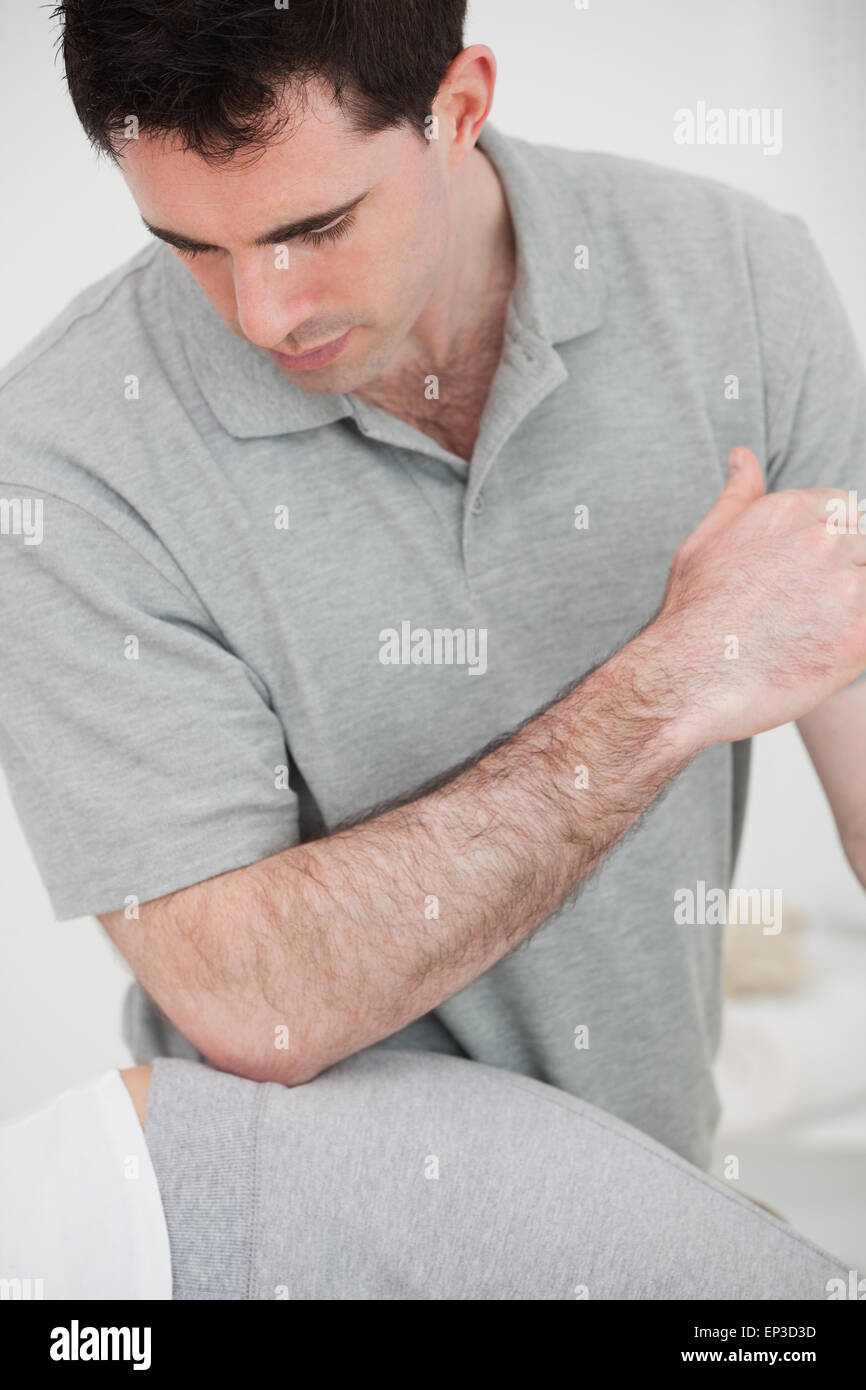

Physiotherapist using his elbow on the hip of a woman Stock Photohttps://www.alamy.com/image-license-details/?v=1https://www.alamy.com/stock-photo-physiotherapist-using-his-elbow-on-the-hip-of-a-woman-82440049.html

Physiotherapist using his elbow on the hip of a woman Stock Photohttps://www.alamy.com/image-license-details/?v=1https://www.alamy.com/stock-photo-physiotherapist-using-his-elbow-on-the-hip-of-a-woman-82440049.htmlRFEP3D3D–Physiotherapist using his elbow on the hip of a woman